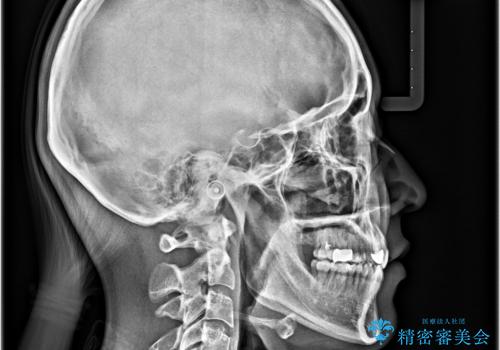

- 前歯のデコボコと口元の突出感を気にして来院された患者様です。

口元の突出感が認められ、更には左右で異なる咬合状態であったため、下顎右側は第二小臼歯を、左側は第一小臼歯を抜去することでバランスを取るような治療計画としました。

また上顎前歯は大臼歯に補綴治療が必要であったため、矯正治療後にオールセラミッククラウンによる補綴治療を行うこととしました。

下顎の抜歯位置を左右で変えることで、最終的に上下正中をほぼ一致させることができました。